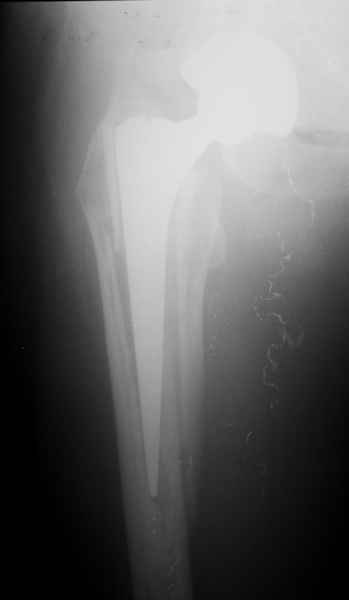

Произведено закрытое удлинение ножки эндопротеза с помощью ретроградного интрамедуллярного стержня. Продолжительность операции 3 часа. Два из них закрытое восстановление длины бедра диистрактором

таз-бедро.

А нельзя ли увидеть и профиль бедра на всем протяжении, т.е. и весь протез, и весь стержень? И фас бы с коленом.

новые снимки